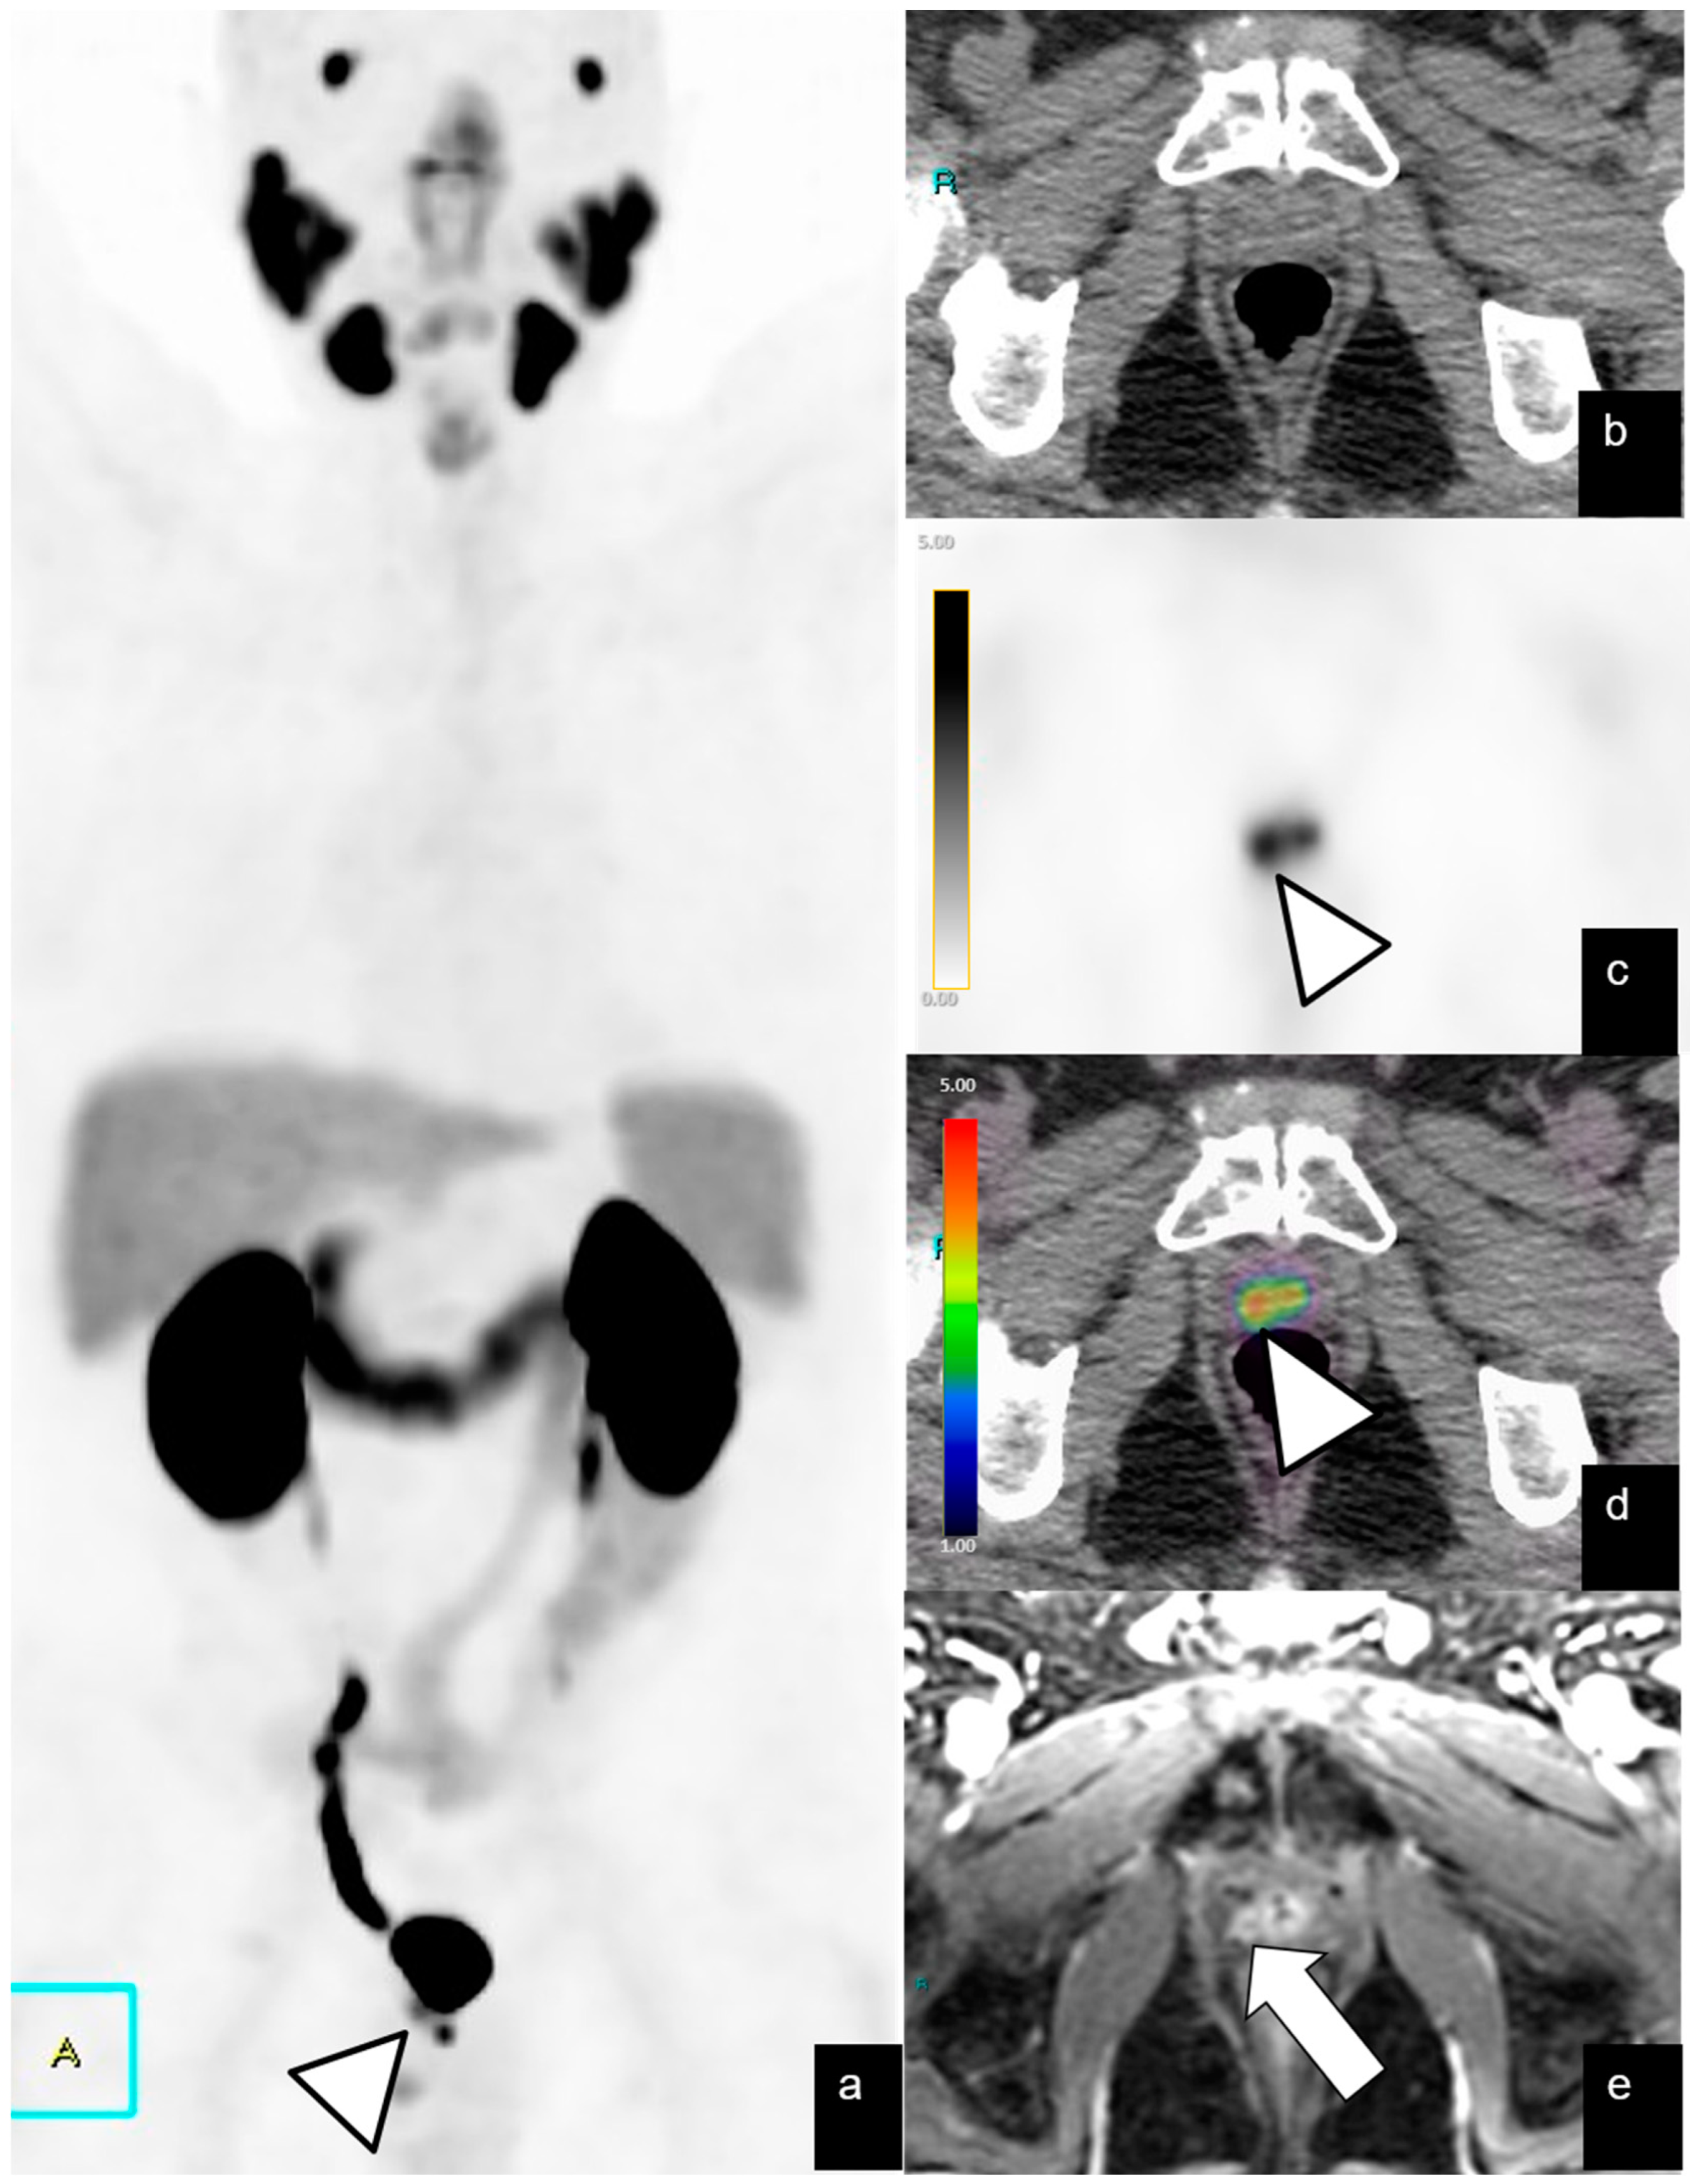

| Local recurrence | 42/128 (32%) | 12 | 2.1–46 | 9.6 | 3–53 |

| Abdominopelvic | 39/128 (30%) | 24 | 1–73 | 7.3 | 2–19 |

| Bone metastases | 20/128 (15%) | 19 | 1.9–70 | ||